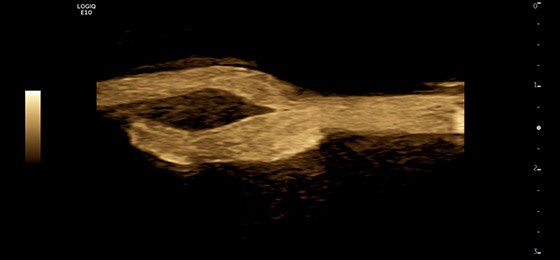

Carotid B-Flow™, L2-9-D